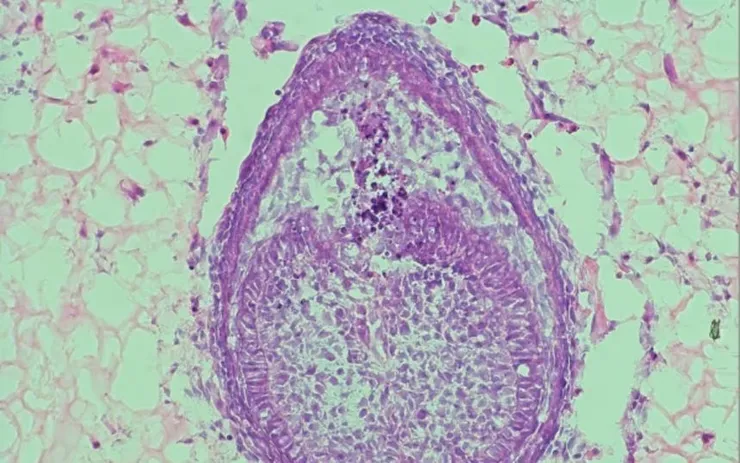

Mẫu lát nhuộm của mô răng được nuôi cấy trong phòng thí nghiệm tại Đại học King’s College London.

Mẫu lát nhuộm của mô răng được nuôi cấy trong phòng thí nghiệm tại Đại học King’s College London. Ảnh: CNN